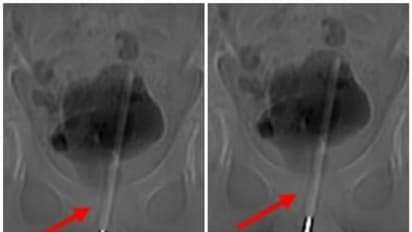

എക്സ്-റേയിൽ തെർമോമീറ്റർ മൂത്രനാളിയിൽ കയറിയതായും അത് കുട്ടിയുടെ മൂത്രസഞ്ചിയിൽ പ്രവേശിച്ചതായും കണ്ടെത്തി. താക്കോൽ-ദ്വാര ശസ്ത്രക്രിയയിലൂടെ കുട്ടിയുടെ മൂത്രസഞ്ചിയിൽ നിന്ന് തെർമോമീറ്റർ പുറത്തെടുക്കുകയായിരുന്നുവെന്ന് ശസ്ത്രക്രിയയ്ക്ക് നേതൃത്വം നൽകിയ ഡോക്ടർമാർ പറഞ്ഞു.

മൂത്രം സംഭരിക്കുന്ന മൂത്രാശയത്തിലേക്ക് അവർ ടിഷ്യൂവിൽ ഒരു ചെറിയ ശസ്ത്രക്രിയാ ദ്വാരം ഉണ്ടാക്കി തുടർന്ന് തെർമോമീറ്ററിനെ ശരിയായ കോണിലേക്കും സ്ഥാനത്തേക്കും കൈകാര്യം ചെയ്യാൻ ചെറിയ ഉപകരണങ്ങൾ തിരുകുകയും കീ-ഹോളിലൂടെ പുറത്തെടുക്കുകയും ചെയ്തു.